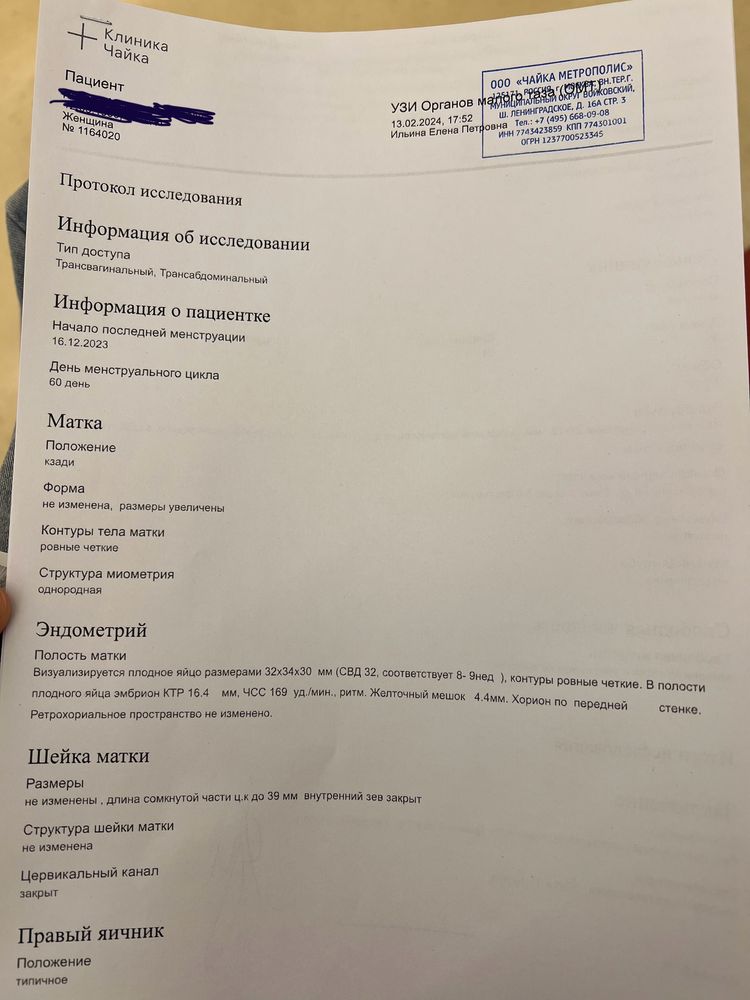

Здравствуйте! Дорогие дамы, прикрепляю 2 узи от 13.02.2024 и от 24.02.2024. Нормально малыш вырос? Узистка странно написала на первом узи, что малыш по ктр на 8 недель и 3 дня, хотя аппарат показывал 8 недель ровно. Сегодня у меня (24.02.2024) 10 недель ровно, а аппарат показал 9 недель и 4 дня. На самом первом узи в 6 недель и 3 дня мне аппарат показывал, что малыш по размерам на 6 недель ровно. То есть, везде стабильно 3 дня разница с акушерским сроком. Сегодня аппарат показал ЧСС 177, но узистка написала в протоколе 171, почему-то.